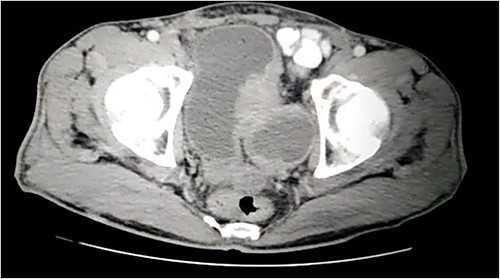

A 57-year-old male was referred to the urology department with hematuria 6 months before. Computed tomographic (CT) showed a mass in the bladder without any other significant results (Fig. 1). Endoscopic examination showed a solid lesion within a large diverticulum where biopsies were performed and the histopathology examination showed UC (invaded the lamina propria, pT1). A radical cystectomy with ileal conduit was performed with extended pelvic lymph node dissection. The histological study indicated the presence of a high-grade UC, which invaded the muscularis propria to the perivesical fat (Fig. 2) with neural and lymphovascular invasion (Fig. 3), but the metastases to pelvic or obturator lymph nodes were absent. After that, he received adjuvant chemotherapy (Paclitaxel), but he could not tolerate the side effects of the drug, which led to the cessation of treatment after only two doses. Two months later, he complained of swelling on the left cheek (Fig. 4) with pain in the left shoulder. Positron emission tomography and CT (PET-CT) showed an unclear, heterogeneous mass that leaches into the skin and adipose tissue underneath it and the left masticatory muscle measuring 40 × 20 mm showing pathological metabolic activity (Fig. 5). In addition to the presence of osteolysis in the posterior arch of the left eighth rib with the formation of a tissue mass extending over 75 × 35 mm showing pathological metabolic activity. Surgical intervention was performed to remove the described masses, and the histological examination demonstrated the presence of UC. Then, he received chemotherapy (Paclitaxel, 6 doses), and unfortunately PET-CT showed a relapse which occurred 4 months later, where the eighth rib was removed and supraclavicular region. Then, he underwent immunotherapy (Nivolumab) and radiation therapy until his death 10 months after the first appearance of cheek metastasis. There was no recurrence in place of the removed mass on the cheek.

CT showing a large bladder diverticulum on the posterior wall with a mass within it.